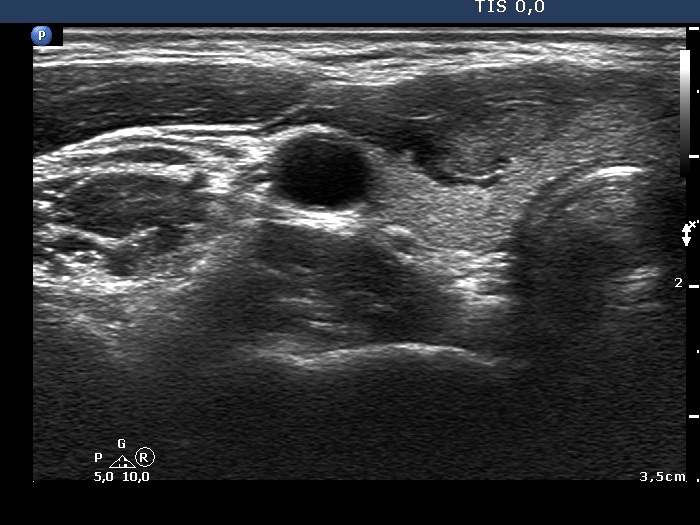

First examination (first row of images):

Clinical presentation: A 31-year-old woman was referred for evaluation of a nodule discovered by herself.

Palpation: a not firm nodule in the isthmus.

Hormonal evaluation: euthyroidism with TSH 0.75 mIU/L.

Ultrasonography. The thyroid was echonormal. There was a small, moderately hypoechogenic lesion in the lower part of the left lobe while a larger nodular area was located in the isthmus. The latter was composed of hypoechogenic and echonormal parts and presented cystic degeneration, as well.

Aspiration cytology of the isthmic nodule disclosed a follicular lesion with signs of hyperthyroidism.

We indicated scintigraphy which revealed an autonomously functioning nodule according to the lesion in the isthmus. We suggested follow-up, yearly TSH determination.